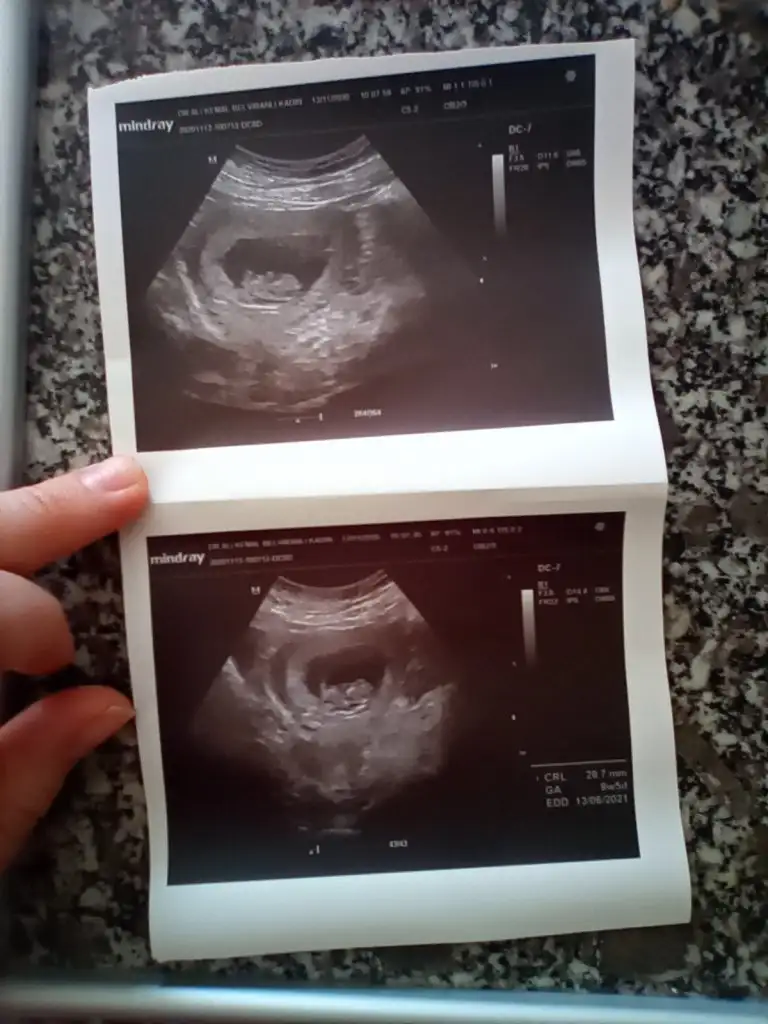

En iyi 11 12 13 haftalar olmalıMerhabagördüğüm kadarıyla tahmin yapıyorsunuz birde bana yorum yaparmısiniz. Eki Görüntüle 2720348

8+5 yazıyor uygun değil nub içinEki Görüntüle 2721344 10 haftalik usg yegenimin bi balar misiniz

Kız gibi sanki emin olamadım başka USG varsa paylaşınİkra meyra banada bakarmısınız12 haftalık resmi

Kız gibi sanki emin olamadım başka USG varsa paylaşınIkra meyra 13 hafta

Kız gibi sanki emin olamadım başka USG varsa paylaşın

Net degil